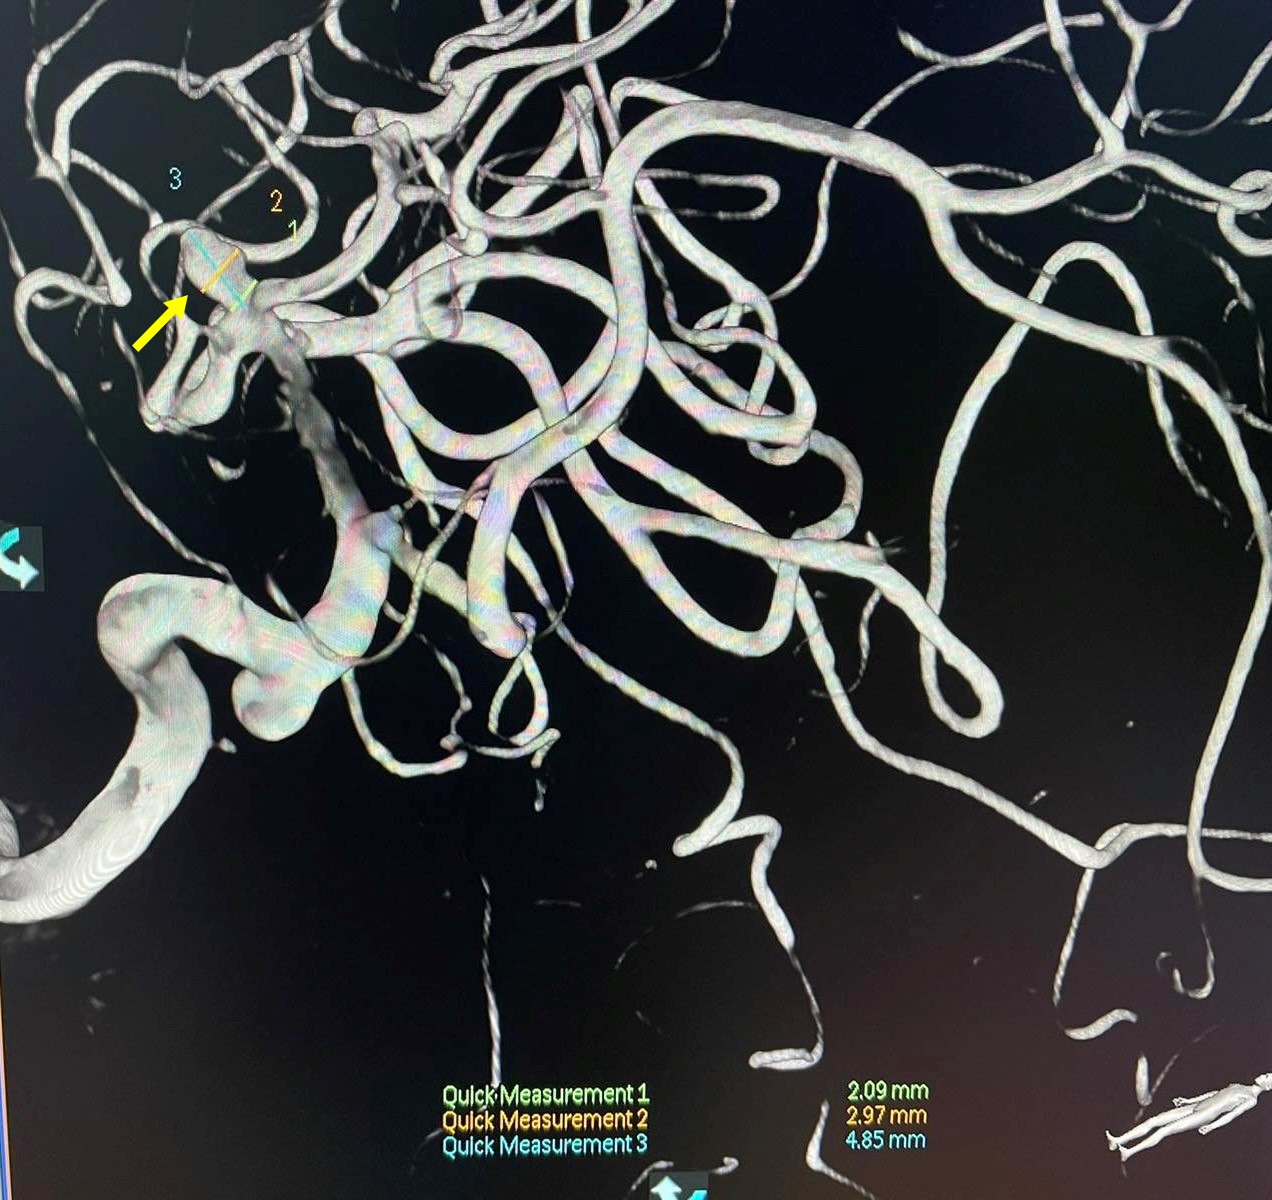

![]() |

| Túi phình trước can thiệp |

ThS.BS Nguyễn Quốc Thái - Khoa Tim mạch can thiệp Bệnh viện Đa khoa tỉnh Quảng Nam cho biết, đây là một bệnh nhân nam tên L.V.D, 46 tuổi, đang ngủ thì đột ngột trợn mắt, gồng cứng người, sùi bọt mép, mất ý thức. Bệnh nhân nhập Bệnh viện đa khoa tỉnh Quảng Nam và kết quả chụp cắt lớp vi tính cho thấy có xuất huyết khoang dưới nhện do vỡ túi phình của động mạch não giữa bên phải.